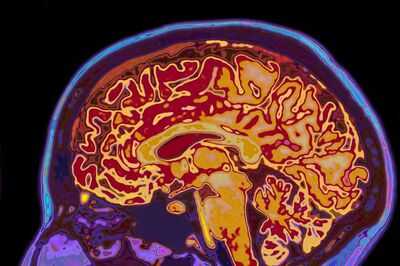

You might have assumed that all brains are roughly the same size. Butscientists suggest this isn't always the case – in fact, the shape of our brain could potentially help detect early signs of dementia.

New research from the University of California explored this concept, analysing over 2,600 brain scans of adults aged 30 to 97. Remarkably, they observed that 'uneven shaping' was particularly prominent in older adults experiencing cognitive decline, which could indicate new markers for identifying dementia risk.

Senior author Niels Janssen explained: "Most studies of brain ageing focus on how much tissue is lost in different regions. What we found is that the overall shape of the brain shifts in systematic ways, and those shifts are closely tied to whether someone shows cognitive impairment."

In the fresh analyses, scientists observed that older adults experiencing cognitive decline showed greater expansion in the 'inferior and anterior parts of the brain', while the 'superior and posterior regions' contracted inward. Adults with 'poorer reasoning' skills were also frequently noted to have 'more pronounced posterior compression', referring to something pressing upon the back.

However, according to the team, one of the study's most striking implications was understanding the 'potential impact of shape changes with age on the entorhinal cortex'. This specifically describes a small but crucial memory base located in the brain.

The study indicates that these shape alterations might physically push this vulnerable area nearer to the rigid base of the skull. The entorhinal cortex is also among the initial regions where tau, a harmful protein associated with Alzheimer’s disease, starts to accumulate.